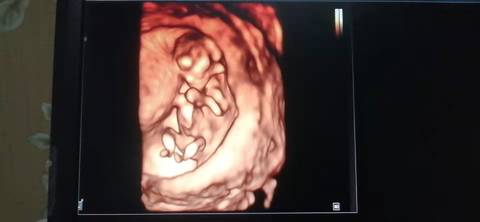

十二周的nt,是不是小棉袄啊? 医生给看宝宝腿的时候生殖器那里是平平的,是女宝吗?我和老公都挺想要小棉袄的

journal_insert_pic_1741079332journal_insert_pic_1741079455journal_insert_pic_1741080014journal_insert_pic_1741080182